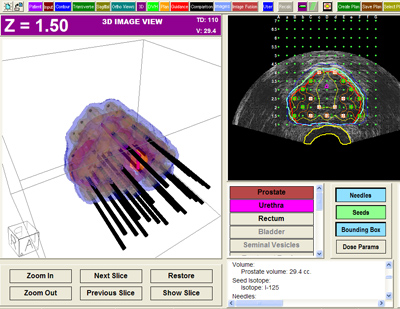

Prostate Brachytherapy Services

OMPC possesses the first Ohio Radioactive Materials License for mobile prostate brachytherapy. We provide the equipment, planning tools and experience to initiate prostate brachytherapy services at your facility immediately.

Using the CMS Interplant ultrasound, planning, and digital stepper system, OMPC provides a true “turn key” approach to prostate brachytherapy services. OMPC is licensed by the state of Ohio to order, receive, and transfer radioactive material for this service. This means no lengthy license application process; no purchasing of equipment; no hiring of additional staff for your facility to begin prostate brachytherapy services! OMPC currently provides services at surgery centers and rural hospitals – the ultimate in convenience and ease for the patient.